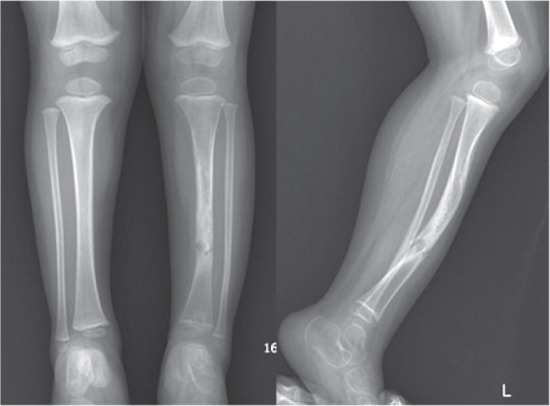

Ложный сустав — это осложнение перелома, при котором нормальный процесс сращения нарушается. Костные отломки не срастаются, а между ними образуется не кость, а «прослойка» из рубцовой или хрящевой ткани. Она не обладает необходимой прочностью, а края костей со временем притираются друг к другу, сглаживаются и даже покрываются подобием суставного хряща. Вокруг формируется капсула, наполненная жидкостью. В результате на месте перелома возникает патологическая подвижность — как будто здесь появился новый сустав, которого не должно быть. Его и называют ложным суставом.

— Укорочение и деформация конечности.